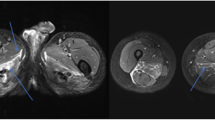

Correlation of muscle quantitative MRI measures with functional rating scales in ATTRv amyloidosis. Representative examples of T1-weighted (T1w) and short tau inversion recovery (STIR) sequences of the thighs and calves of two patients affected by ATTRv amyloidosis with moderate (left) and severe (right) disease. The patient with greater disability (right) has more prominent fat infiltration and a higher water T2 content (A). Moderate to strong positive correlation was observed between mean fat fraction (FF) and water T2 (wT2) at thigh (purple) and calf (blue) level and Polyneuropathy Disability (PND) score (B), Neuropathy Impairment Score (NIS) (C), and NIS-lower limb (NIS-LL) (D)

Muscle quantitative MRI imaging: thigh and calf compartments in ATTRv amyloidosis. Fat fraction (FF) and water T2 (wT2) were not significantly different between thigh and calf level (A). Fat substitution prevailed in the medio-posterior thigh compartment compared to the anterior region while no difference was seen at calf between the antero-lateral and posterior region (B)